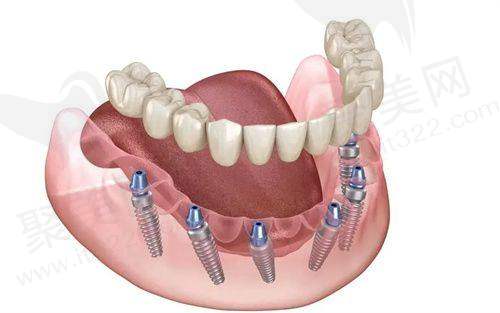

all-on-4种植牙

all-on-6种植牙